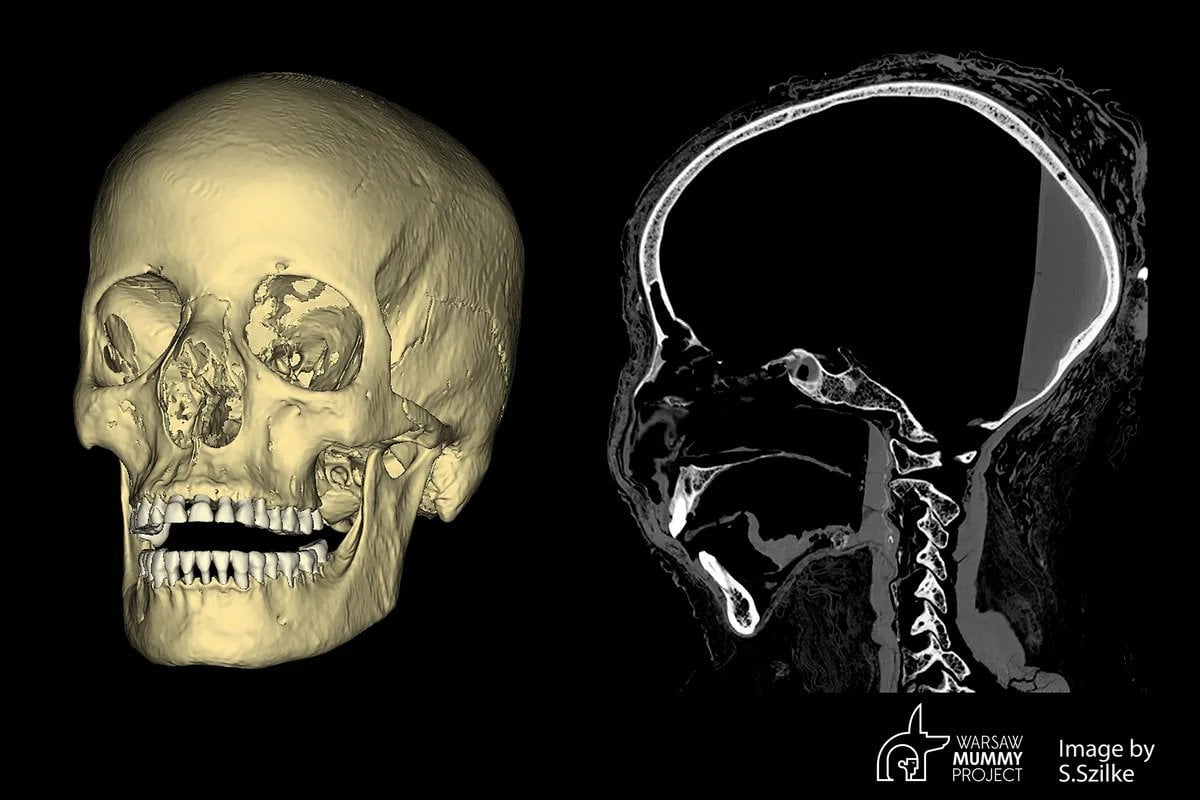

Nie było natomiast jasne, w jakich okolicznościach doszło do śmierci kobiety. Aby odpowiedzieć na to pytanie, archeolodzy wykonali tomografię komputerową jej czaszki. Skany wykazały istnienie nietypowych sygnatur w kości, wskazujących na możliwość chorowania kobiety na raka. Jednym z najbardziej prawdopodobnych kandydatów wydaje się rak nosogardła – rzadko spotykany, lecz występujący również współcześnie.

Na tomografii komputerowej, w kości za lewym oczodołem, widać niewielką zmianę patologiczną, o średnicy około 7 milimetrów, okrągłą strukturę otaczającą pustą przestrzeń. Jest to najprawdopodobniej zmiana wykonana przez guz, być może miejsce przerzutowe. […] Ponadto w kościach twarzy znajdują się duże ubytki, w tym w jamie nosowej, zatokach szczękowych, części podniebiennej kości szczękowych. wyjaśnia Wojciech Ejsmond z Warsaw Mummy Project